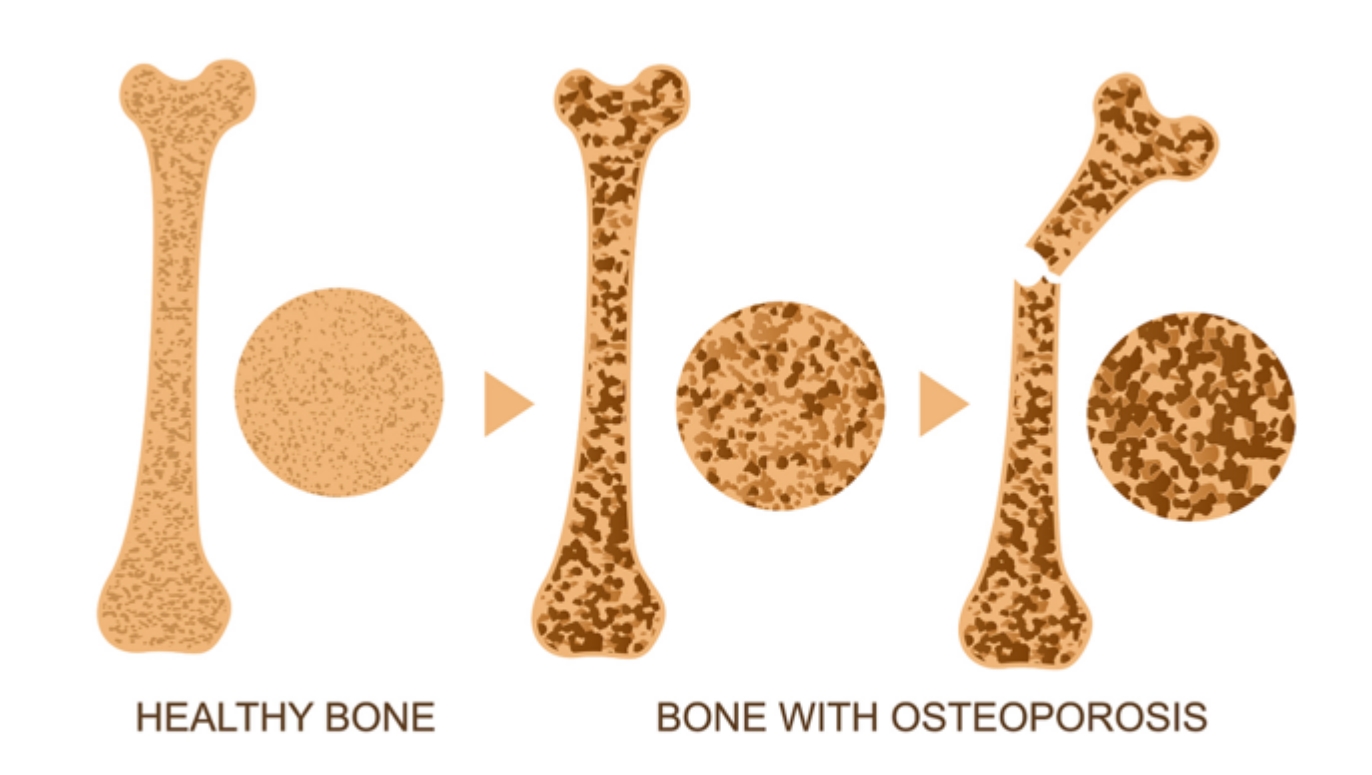

骨质疏松与病理性骨折